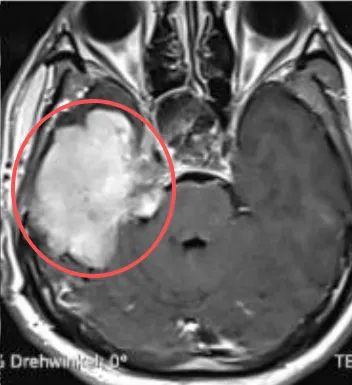

一次偶然的头晕,他查出岩斜区脑膜瘤。一场开颅手术,开启了与之长达12年的艰难抗争。

意料之中,这个切不干净的良性肿瘤,又再次生长。“既然肿瘤可能复发,为什么不多切一点?”陷入困境中的林先生,为了遏制肿瘤生长,他两度进行伽马刀,肿瘤依然顽固。眼看着治疗后仍未好转,甚至右侧耳朵里长出奇怪“肿瘤”,失聪……而在最近的两年里,这个残留的脑膜瘤疯狂生长,已侵犯多个区域。

位置深、粘连重、结构复杂的脑瘤,其手术犹如“虎口拔牙”。有时候别说多切,连切都是问题。于是,当得知巴教授来华,林先生格外珍惜这次机会。而与林先生处境类似的疑难位置胶质瘤、脑海绵状血管瘤、脊髓髓内肿瘤、松果体区肿瘤、颅咽管瘤等患者,也寄希望于即将到来的巴教授。